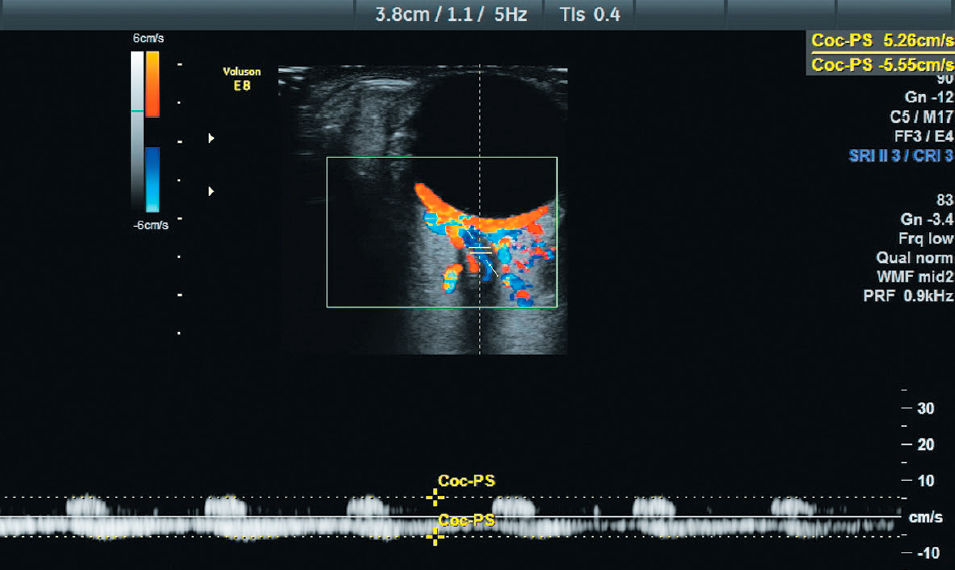

Preoperative mean PSV and EDV were 12.4 ± 3.4 and 4.2 ± 1.4 cm/s, respectively. At 40 and 60 mmHg control points, blood flow velocity was decreased in all patients in the study group (see Fig. 5). At 40 mmHg control point, mean PSV and EDV were 12.0 ± 3.9 and 3.3 ± 1.2 cm/s, respectively. At 60 mmHg control point, mean PSV decreased to 10.2 ± 3.6 cm/s, whereas EDV significantly decreased to an average of 1.1 ± 1.1 cm/s and was not recorded in 3 cases (see Fig. 6).

Fig. 6. Doppler image of blood flow in the central retinal artery and central retinal vein at intraocular pressure of 60 mmHg. Peak systolic velocity is decreased (PSV 5.26 cm/s); the diastolic component is not observed (EDV 0).